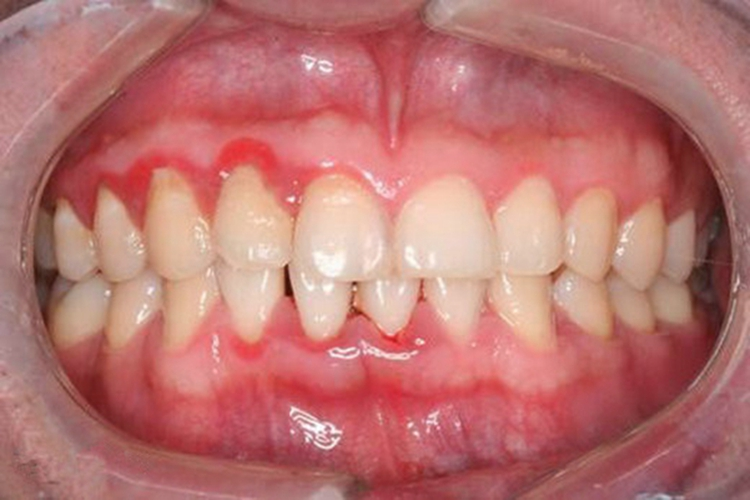

牙结石:可有牙齿发黄、口臭、牙龈出血等症状表现。

牙周炎:患者可有牙龈红肿、齿间出血、牙齿松动等症状表现。

牙周炎:对于症状较轻的牙周炎疾病,可以通过清除牙石,配合使用复方氯已定漱口水,口服甲硝唑片等消炎药物进行治疗。对于症状较重的牙周炎,可通过翻瓣术、植骨术等手术方式进行治疗。